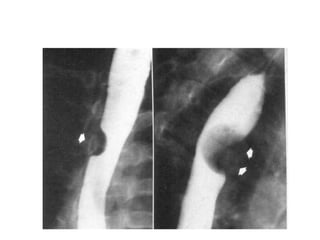

Giãn tĩnh mạch thực quản

• Ung thư thực quản